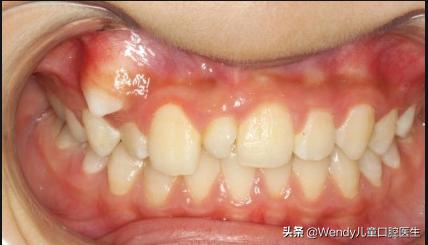

前天小泽妈带着小泽来看牙,乳牙按时掉了可惜新长出的恒牙怎么看都不对劲,形态怪异,一般这种情况首先考虑多生牙,建议拍摄全景片。果不其然,新长出的的确是多生牙,除外还发现颌骨里长了另一颗倒置的多生牙,这颗多生牙斜着挡在恒牙的上方,对恒牙萌出一定有影响,建议拔除。

多生牙的形态变异很多,发育完整型多生牙与正常的牙齿形态相似,但最常见的还是发育不足的畸形牙。如果长在牙列中有碍美观。

但大多数多生牙的发生都是因为有碍美观,才被家长们发现并被处理。